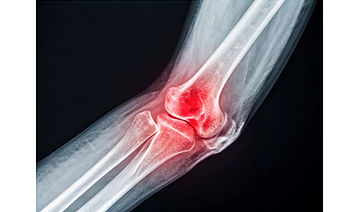

ELBOW INJURIES

Elbow Dislocation

Also not that common... it does still happen. The injury happens when the bones of the elbow are forced out of place and is VERY painful.

Ligament Injury

Ligaments help to keep joints stable and when injured hat can be stretched or torn. Common causes can include: falls, landing on outstretched arm, contact sports or possible heavy lifting.